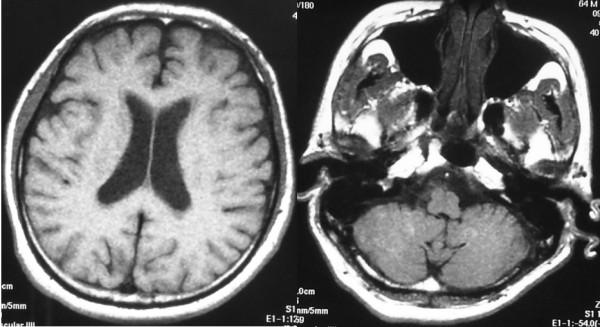

Since the patient presented with a slightly decreased level of consciousness 2 months after surgery, he was subjected to MRI scanning of the brain and spinal cord, which revealed disseminated lesions in the medulla oblongata. The patient died of pneumonia and sepsis caused by methicillin-resistant Staphylococcus aureus 5 months after surgery.

术后2个月患者出现意识水平略有下降,遂对其进行脑和脊髓的MRI扫描,结果显示延髓有播散性病变。患者术后5个月死于耐甲氧西林金黄色葡萄球菌引起的肺炎和败血症。